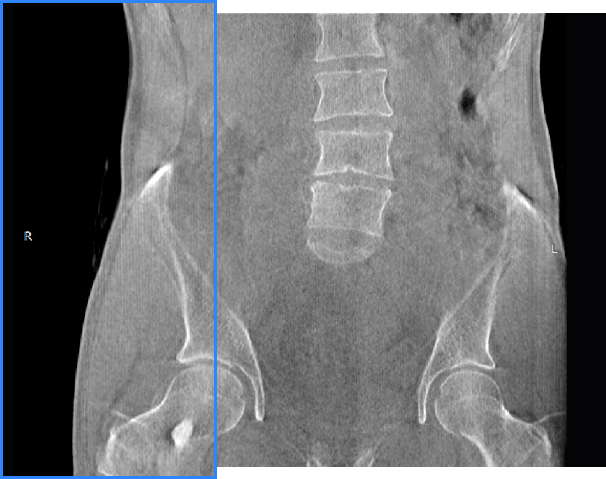

• 髋关节

FOV最大350mm

支持双腿或双侧髋关节扫描 | 方便对比,降低漏诊误诊

FOV 250mm

FOV 350mm